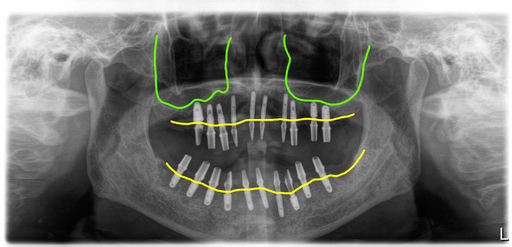

상악에 임플란트주위염이 있는 임플란트와 남은 자연치들을 모두 제거한 후 10개의 임플란트를 식립했고, 아래 전체적으로 흔들리는 보철과 치아들을 제거한 후 임플란트 10개를 식립했습니다.

식립한 임플란트 모두 초기고정이 좋아 바로 지대주를 연결해서 스캔한 후 디자인해서 PMMA로 밀링해서 수술당일 임시치아를 완성해서 세팅해 드렸어요.

수술후 4개월 차에 최종보철을 만들기 위한 스캔을 했고 맞춤지대주에 지르코니아 브릿지타입의 보철을 만들어서 완성했어요.

보철은 가능한 너무 뚱뚱하지 않게 만들어서 위생관리에 도움이 되도록 했고, 치간치솔을 사용할 수 있도록 만들었습니다.